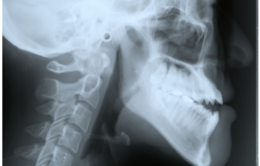

①上顎と下顎の関係

・歯は上下の顎の上に植わっているので、顎がズレると歯並びに大きな影響があります。例えば上顎が大きかったり下顎小さかったりがすると上顎前突(出っ歯)に、その逆であると下顎前突(受け口)になってしまいます。矯正歯科では上の写真のような頭部X線規格写真(セファロ)を撮ることにより顎のずれを評価します。

・子どもでは顎の成長予測をして治療を行いますが、症例によっては成長が終わるまで安心できないこともあります。